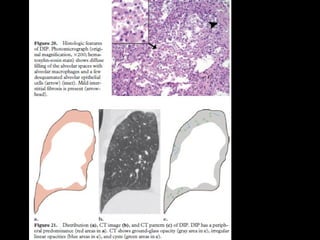

RB-ILD • RB Asintomático,hallazgo • Representan un continuo por la injuria del tabaquismo • Overlap • RB ILD se asocia más a fumadores • DIP: incluye drogas, polvo

CT • Nódulos centrolobularesLS • Vidrio esmerilado • Atrapamiento aéreo • Engrosamiento septal interlobular • DD: neumonitis por hipersensibilidad subaguda, DIP y NSIP

• Biopsia: bronbquiolitisacumulación intraluminal de macrófagos pigmentados

DIP • “alveolar macrophagepneumonia” • Vidrio esmerilado • LI y subpleural • Quistes aéreos, panalziación poco frecuente • DD: RB. NSIP: ausencia de fibrosis, bq x tracción • LBA: macrófagos